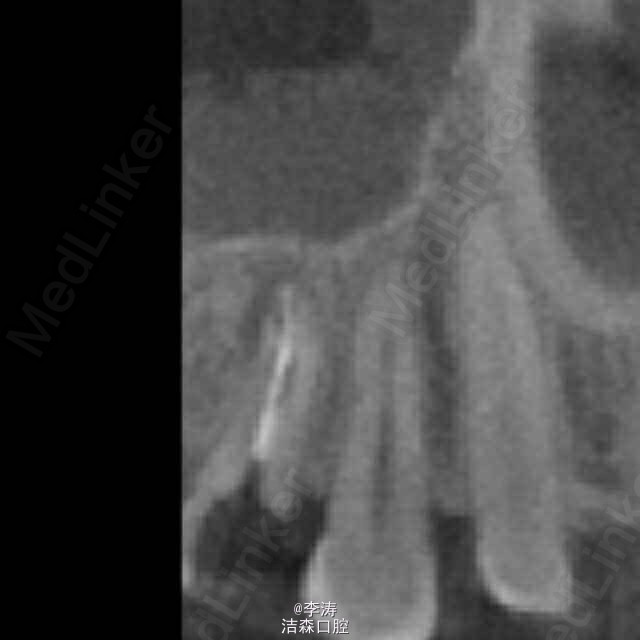

过台阶根管再治疗一例

15牙因根管治疗后牙折裂,行根管再治疗

年轻恒牙;根管再治疗;消除台阶